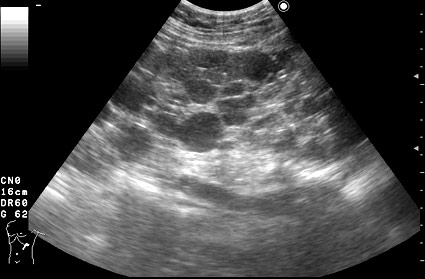

АДПКБП, сонограмма правой почки женщины 37 лет. Почка увеличена, паренхима замещена кистами различных размеров.

Ультразвуковая диагностика АДПКБ почек чаще всего не вызывает трудностей: почки значительно увеличены в размерах, определяется множество кист, от маленьких до нескольких сантиметров в диаметре. Кисты выглядят анэхогенными, при наличии примеси кровянистых и гнойных масс содержимое кист становится акустически непрозрачным, мутным. Полостная система почки дифференцируется плохо, обнаружение конкрементов чаще всего затруднено.